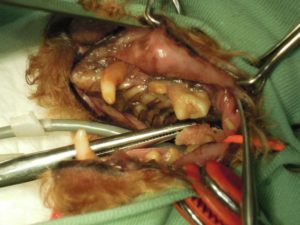

9.左側下顎も全て抜歯しました。

顎先が細くやせた状態になっています。